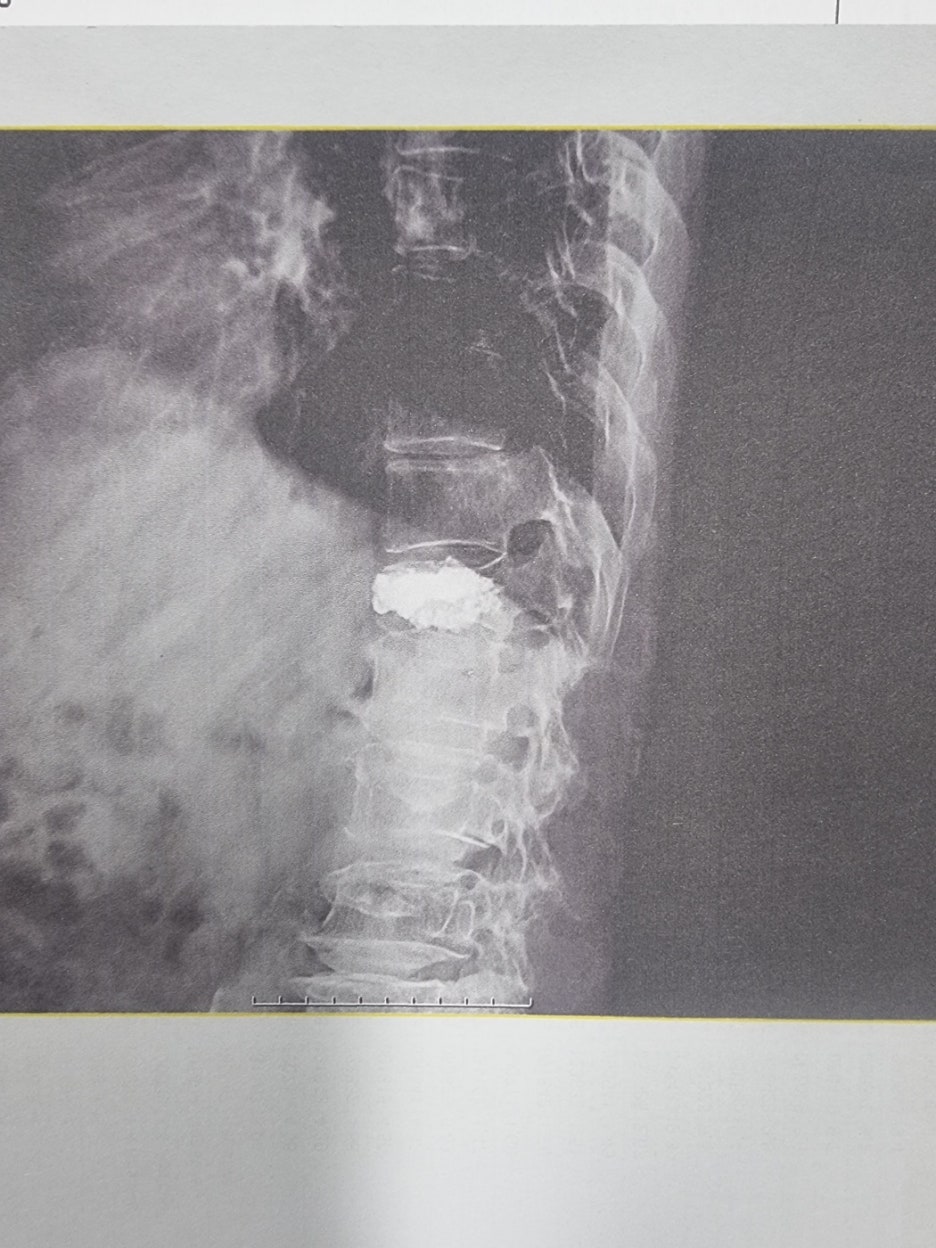

고객은 흉추 12번 압박골절 부위에 시멘트 삽입하는 척추 성형술 수술을 시행하였고, 이후 계속적인 치료후에도 방사선 검사상에 척추골절 압박정도가 심하여 압박율이 30%이상 되었습니다.